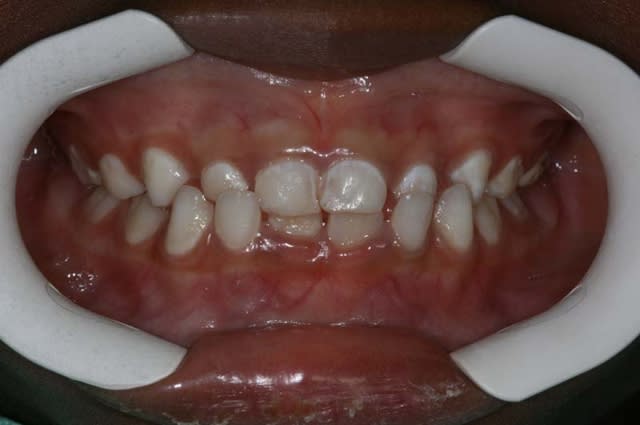

Fillette de 5 ans

Vous feriez quoi ?